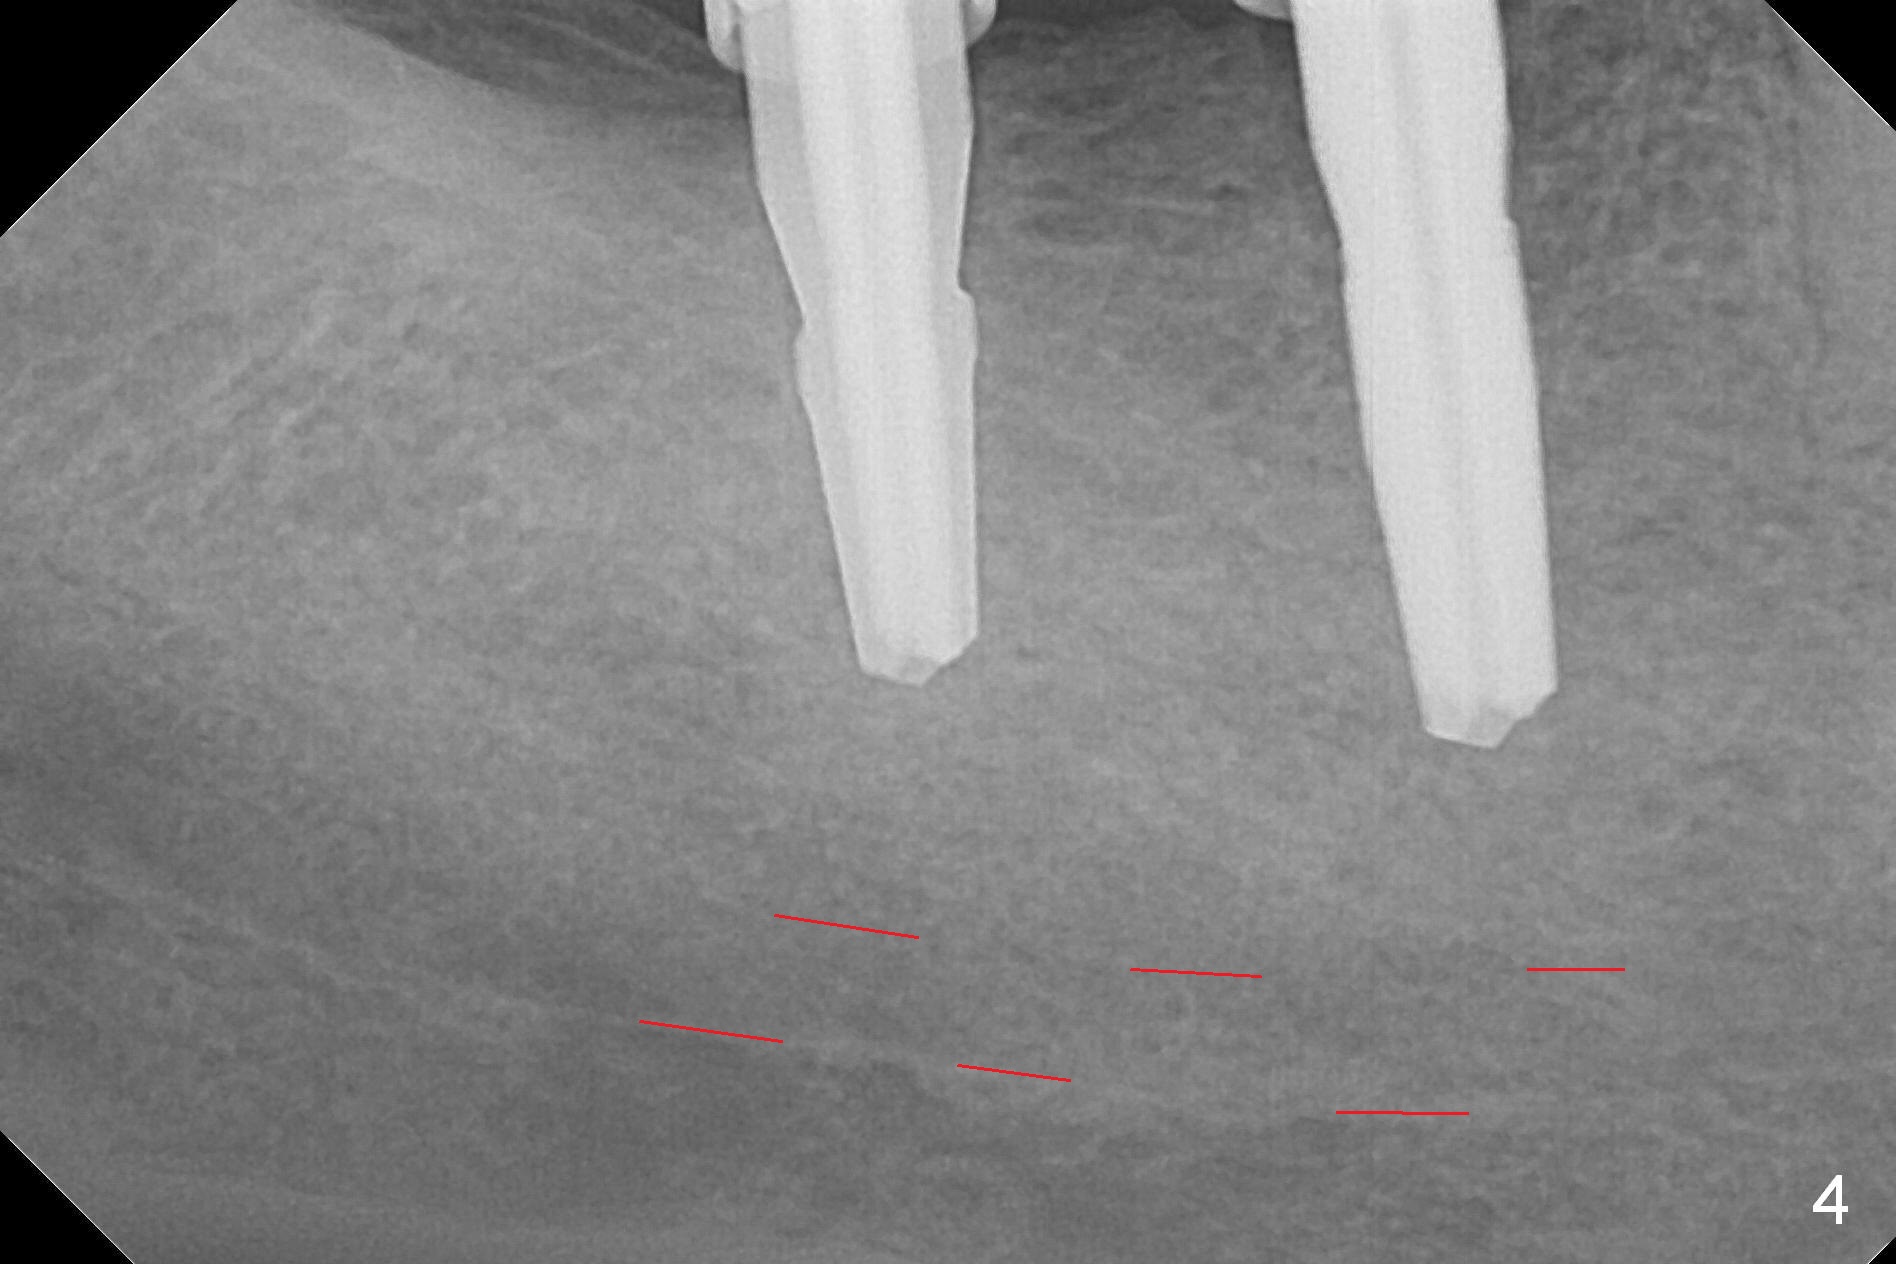

The supraerupted tooth #2 is adjusted using the lower right surgical stent.  Osteotomies are initiated by using starter drill through surgical stent over the ridge (Fig.1) prior to incision.  The initial depths are 10 and 12 mm at the sites of #31 and 30, respectively (Fig.2).  The new sensor with the existing sensor holder cannot reach the deep portion of the lingual vestibule (Fig.2,3).  Without the sensor holder, the #2 sensor with rounded corners has no problem showing the Inferior Alveolar Canal (Fig.4 red dashed line).  The two implants (5x12 and 5x14 mm, Fig.5) are placed with >50 Ncm.  Cemented abutments are immediately placed (6.8x4(2) and 6.8x4(3) mm) to reduce suture tension (after autogenous bone graft and collagen dressing) and hold periodontal dressing in place.  The wound does not heal completely 15 days postop (Fig.6).  The patient reveals that he smokes 1/2 pack per day.  There is crestal bone resorption 4 months postop (Fig.7 *).  It appears that for smokers, implants should be smaller, placed deeper and buried.  In addition, his oral hygiene is not good.